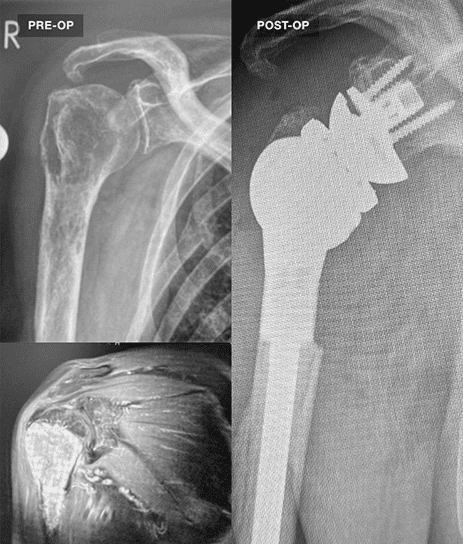

For fracture and revision treatment

The system offers a set of modular Proximal Bodies in several sizes and heights to be paired with a broad range of Modular Stems, available in different diameters and lengths as well as different surface and coating options for cemented and cementless fixation.

The Proximal Bodies’ spiked surface, together with m-l and a-p holes for suture fixation, allow for stable and physiologic tuberosities reattachment. The modular concept of the fracture components supports the surgeon in achieving adequate joint restoration even in cases with poor anatomical landmarks.1